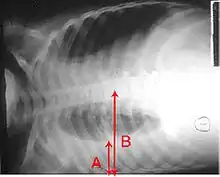

Lung ultrasound may also be useful in helping to make the diagnosis.[67] Ultrasound is radiation free and can be done at bedside. However, ultrasound requires specific skills to operate the machine and interpret the findings.[34] It may be more accurate than chest X-ray.[68]

Pneumonia seen by ultrasound[69]

Right middle lobe pneumonia in a child as seen on plain X-ray